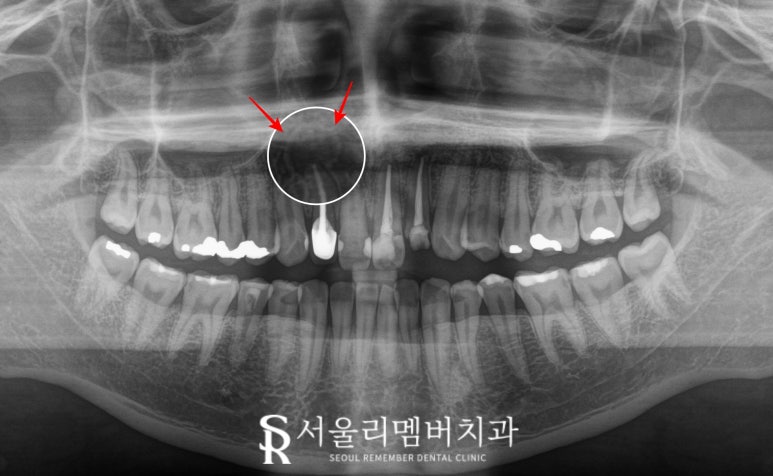

2025.05.22

오른쪽 위 측절치(12번)에 불편감이 존재하며,

파노라마 엑스레이를 찍어보니

치근단에 농양(apical abscess)이

관찰되었습니다.

해당 치아는 이전에 신경치료를 받았으나

치유가 잘 이루어지지 않아

염증이 계속 존재하다 보니

이렇게 뼈를 녹이게 된 것이죠.